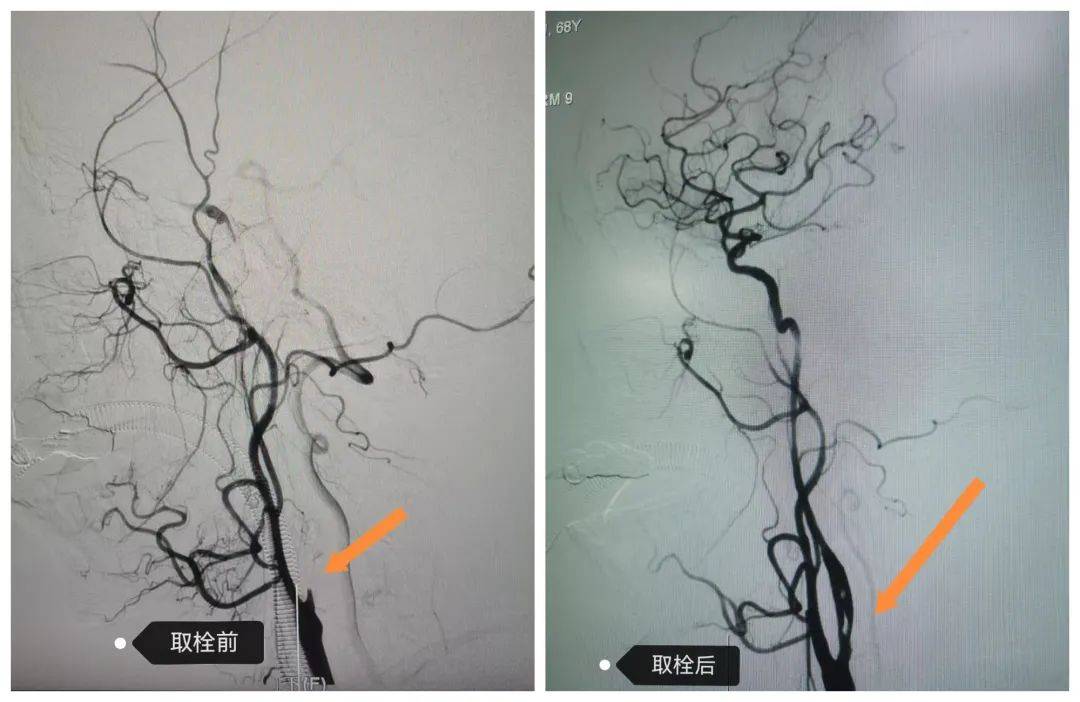

68歲的戶大爺突發(fā)言語不清、左側(cè)肢體無力3小時后入院,值班醫(yī)師衛(wèi)小冬通過頭顱核磁確診大面積腦梗死,且病情有進一步惡化風險。在劉彥書主任帶領下,介入團隊于入院 2 小時內(nèi)完成術(shù)前準備并實施顱內(nèi)取栓術(shù)。目前患者癥狀持續(xù)改善,康復出院指日可待。